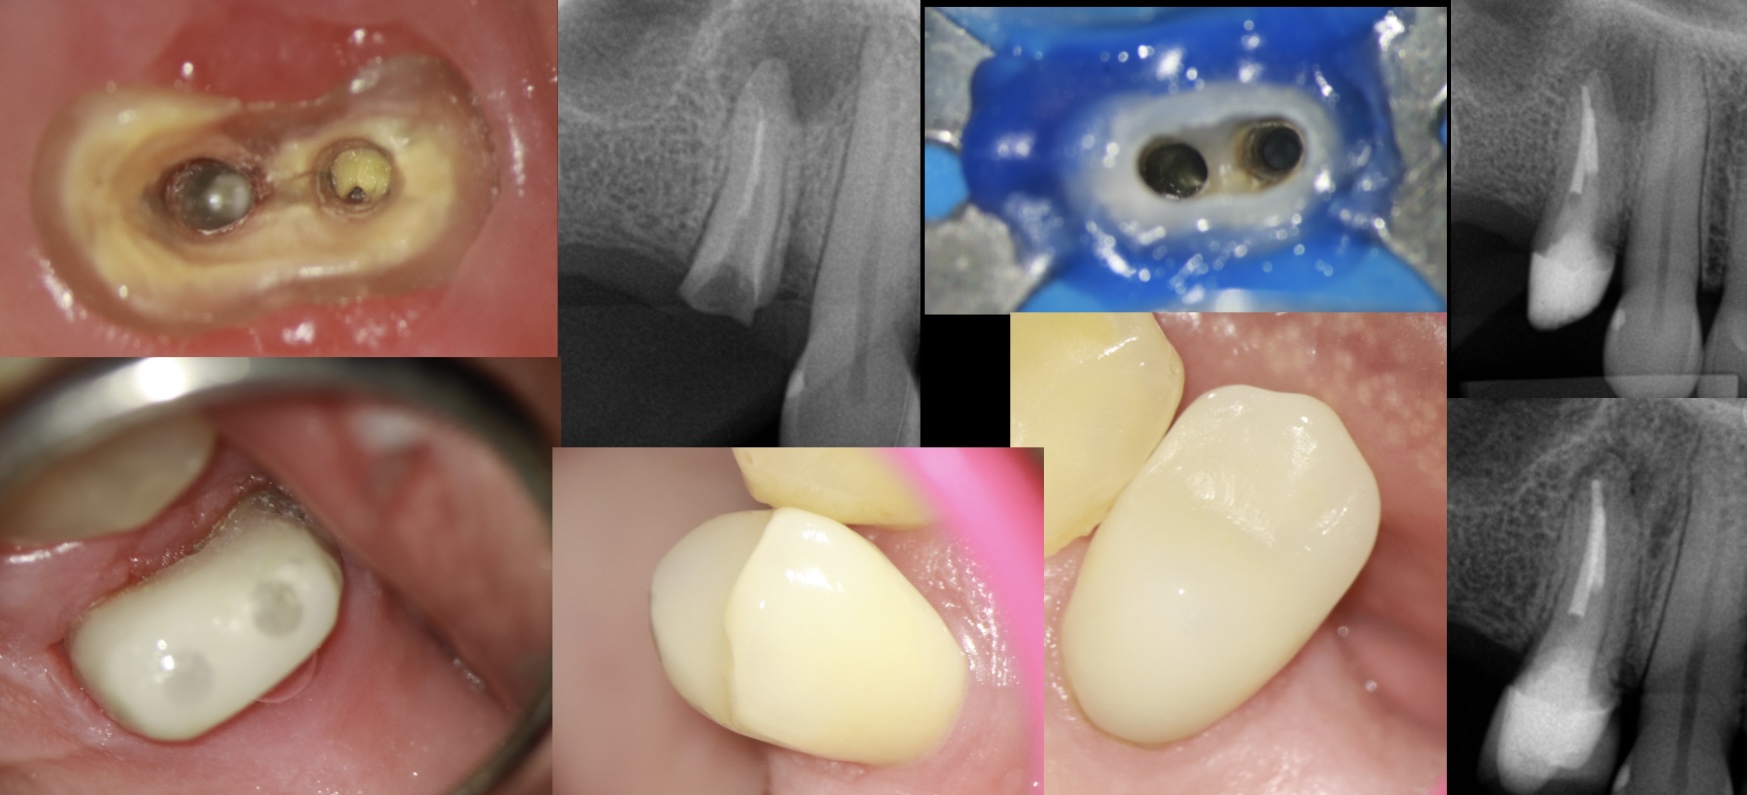

Outros usos:

Em pacientes com dentição mista você pode usar para ajudar no isolamento. Colocando o adesivo BeautiBond Xtreme e a resina Beautifil Flow Plus 00 em região palatina ou vestibular. Funciona super bem (figura 3).

Em caso de margens subgengivais em dentes, que possuem dentes adjacentes, para erguer suas paredes e ajudar na reconstrução. Você pode usar o mesmo protocolo usando está resina citada no artigo e poderá inclusive por um grampo de isolamento em cima deste mesmo dente (figura 4, 5, 6 e 7).